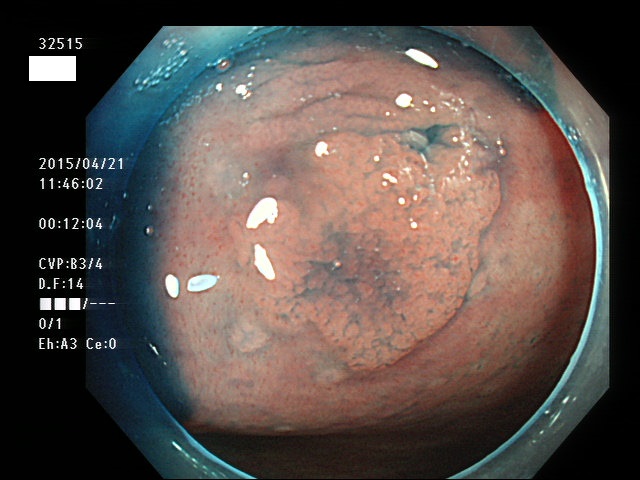

上記100名より抽出した平坦・陥凹型腺腫(=癌化の危険が高いが見落としやすい病変)の内視鏡写真

32500 32502 32506 32508 32509 32510 32512 32515 32517 32520 32521 32522